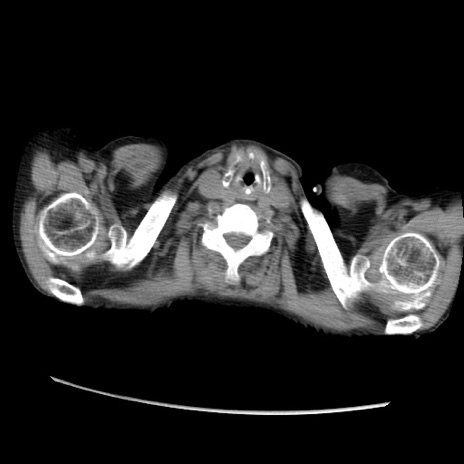

症例31(横断像)

【症例】80歳代 女性

【主訴】腹部膨満感

【現病歴】他院にて肝硬変にてフォロー中。1週間前から便秘、腹部膨満感、臍部腫瘤あり受診となる。

【既往歴】肝硬変

【身体所見】腹部膨隆あり、皮膚変化なし、疼痛なし。

【データ】WBC 4600、CRP 0.25